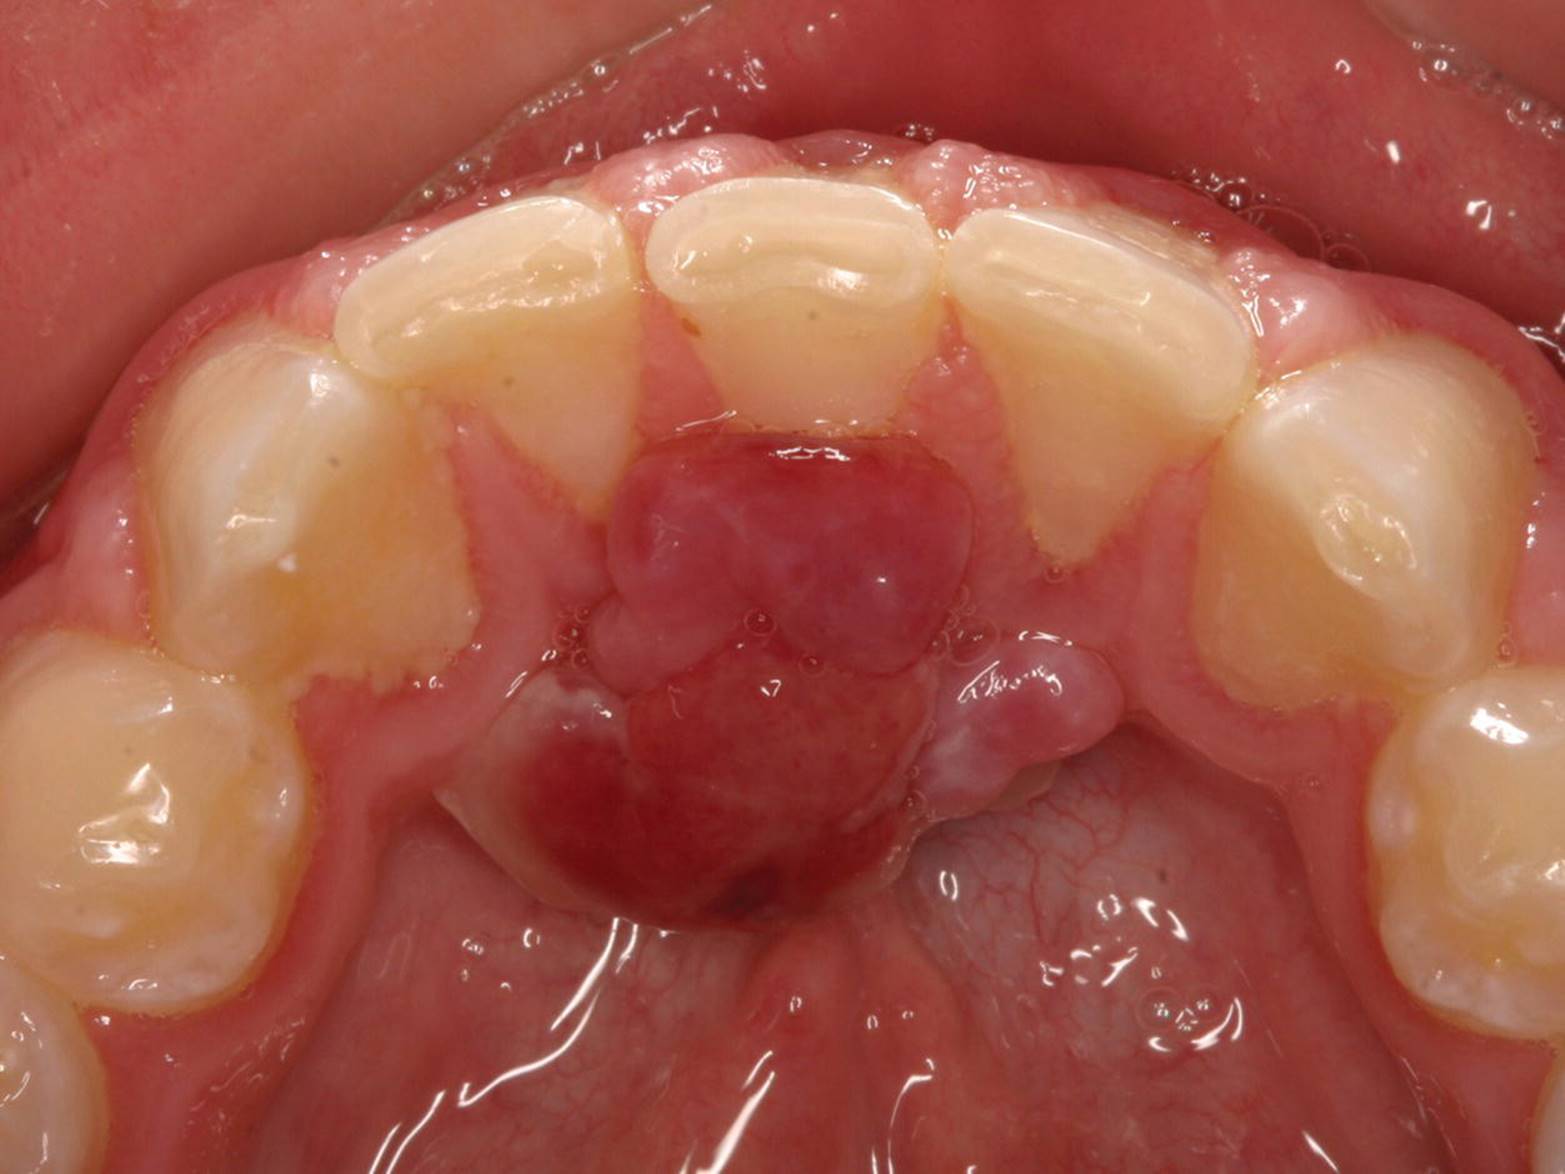

Epulides are by definition tumor‐like hypertrophic tissue formations located on the gingival mucosa. The etiology is often trauma or irritation in connection with tooth eruption or exfoliation. The size may vary from some millimeters up to several centimeters in diameter. They differ in surface texture, consistence and color, depending on the tissue composition. Pyogenic granuloma, peripheral calcifying granuloma, and peripheral giant cell granuloma (Figures 15.19, 15.20 and 15.21) are all examples of epulides. The treatment is excision, and the final diagnosis is confirmed by histopathologic analysis.

Figure 15.20 Peripheral calcifying granuloma.